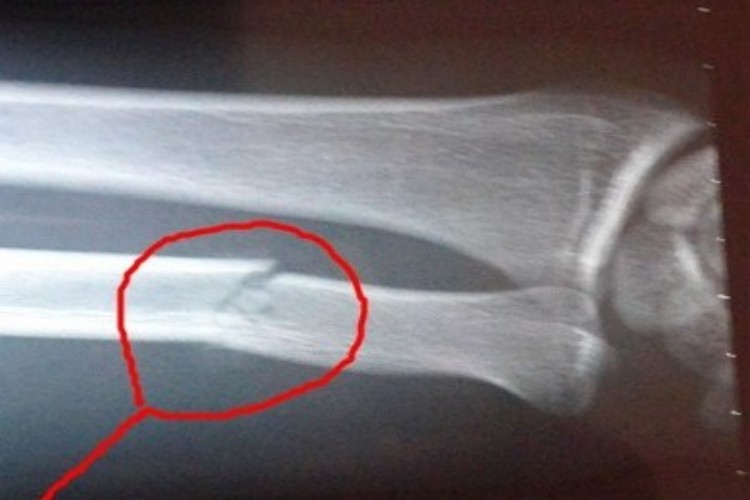

左手尺骨骨折可见局部红肿、疼痛、活动受限,X线检查骨的完整性和连续性中断。

左手尺骨骨折表现为左手臂局部出现红肿、疼痛,无法正常活动,通过X线检查见患处骨的完整性和连续性中断,两骨折端相互摩擦时有骨擦感,严重时骨折端与外界相通。此外,也可仅为尺骨出现裂缝,局部自觉疼痛,在手臂活动时加剧,伴有明显压痛。

左手尺骨骨折的治疗首先要通过影像学检查确定骨折的具体部位,并根据病情进行手法或切开复位,加以石膏固定。术后要对患肢进行制动以保证骨骼愈合、防止畸形。在不影响固定的前提下,要尽快进行适当的舒展活动,可以促进血液循环、减少肌肉萎缩。